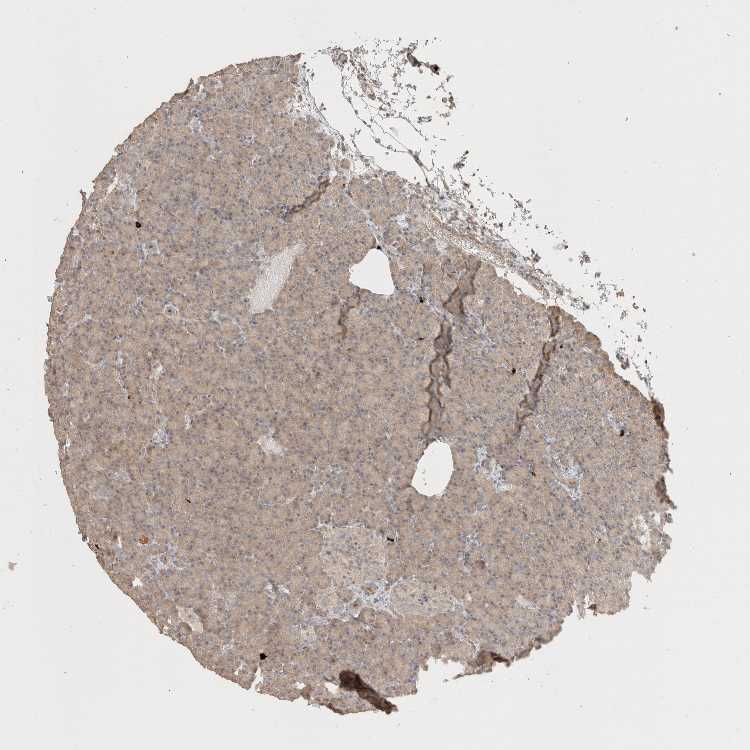

PANCREAS - Antibody stainingi

Antibody staining in the annotated cell types in the current human tissue is reported as not detected, low, medium, or high, based on conventional immunohistochemistry profiling in selected tissues. This score is based on the combination of the staining intensity and fraction of stained cells.

Each image is clickable and will lead to virtual microscopy that enables deeper exploration of all samples and also displays staining intensity scores, fraction scores and subcellular localization as well as patient and tissue information for each sample.

Antibody HPA018892Antibody HPA072690Antibody CAB009820Antibody CAB020718

Exocrine glandular cells LowMediumLowLow

Pancreatic endocrine cells MediumNot detectedLowNot detected